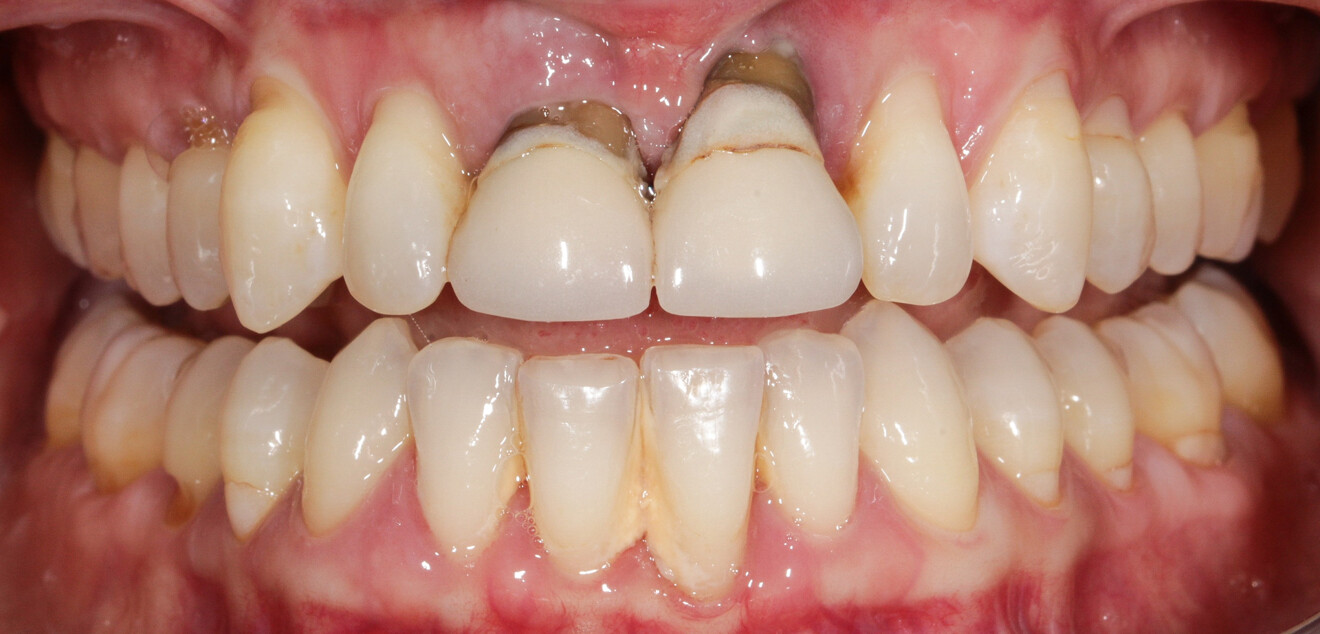

Une patiente de 49 ans nous a été adressée par l’un de nos confrères pour le remplacement de ses quatre incisives maxillaires (Fig. 23). Dans un contexte parodontal avancé, ses incisives centrales présentent une mobilité terminale (classe IV) elle n’ose plus les brosser de peur de les perdre lors de la manoeuvre. La patiente ne présente pas de problèmes de santé particuliers.

À l’examen, on observe une mobilité des quatre incisives maxillaires, une insuffisance osseuse verticale et horizontale, associées notamment au niveau de 11 et 21, la présence de plaque, de tartre et d’inflammation gingivale, surtout au niveau du bloc antérieur maxillaire. On note également la présence d’une dent de sagesse (dent 18) perdue (Figs. 24–26).

Le but du traitement est le remplacement des quatre incisives par un bridge implanto-porté de 12 à 22. Le plan de traitement mis en place est le suivant : extraction des deux incisives centrales et réalisation d’un bridge provisoire dento-porté fixe de 12 à 22 ; trois mois de temporisation permettant la cicatrisation des tissus mous, ainsi que la mise en oeuvre de la thérapeutique parodontale (Fig. 27) ; extraction de 12, 22 et 18, mise en place des implants, reconstruction de la crête (avec les racines extraites), mise en place d’un bridge provisoire fixe de 12 à 22, transvissé sur les deux implants.